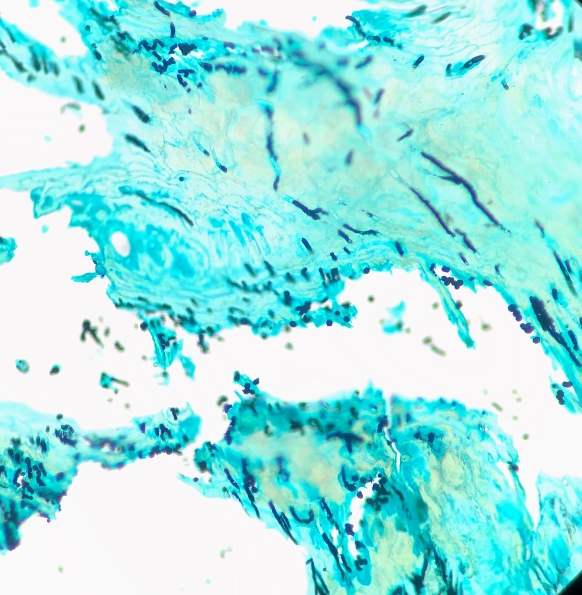

조갑사상균증은 거창한 단어처럼 보일 수 있지만, 간단히 말해 발가락과 손가락의 손발톱에 영향을 미치는 곰팡이 감염을 말합니다.

손톱이 노랗고 부서지기 쉬우며 평소와 다른 모습으로 변하는 성가신 불청객을 아시나요? 네, 바로 조갑사상균증입니다.

- 곰팡이 감염: 식물이 자라기 위해 물이 필요한 것처럼 곰팡이도 번성하기 위해 따뜻함과 수분이 필요합니다. 곰팡이는 손톱 밑에서 서식하는 것을 좋아하기 때문에 감염으로 이어질 수 있습니다.